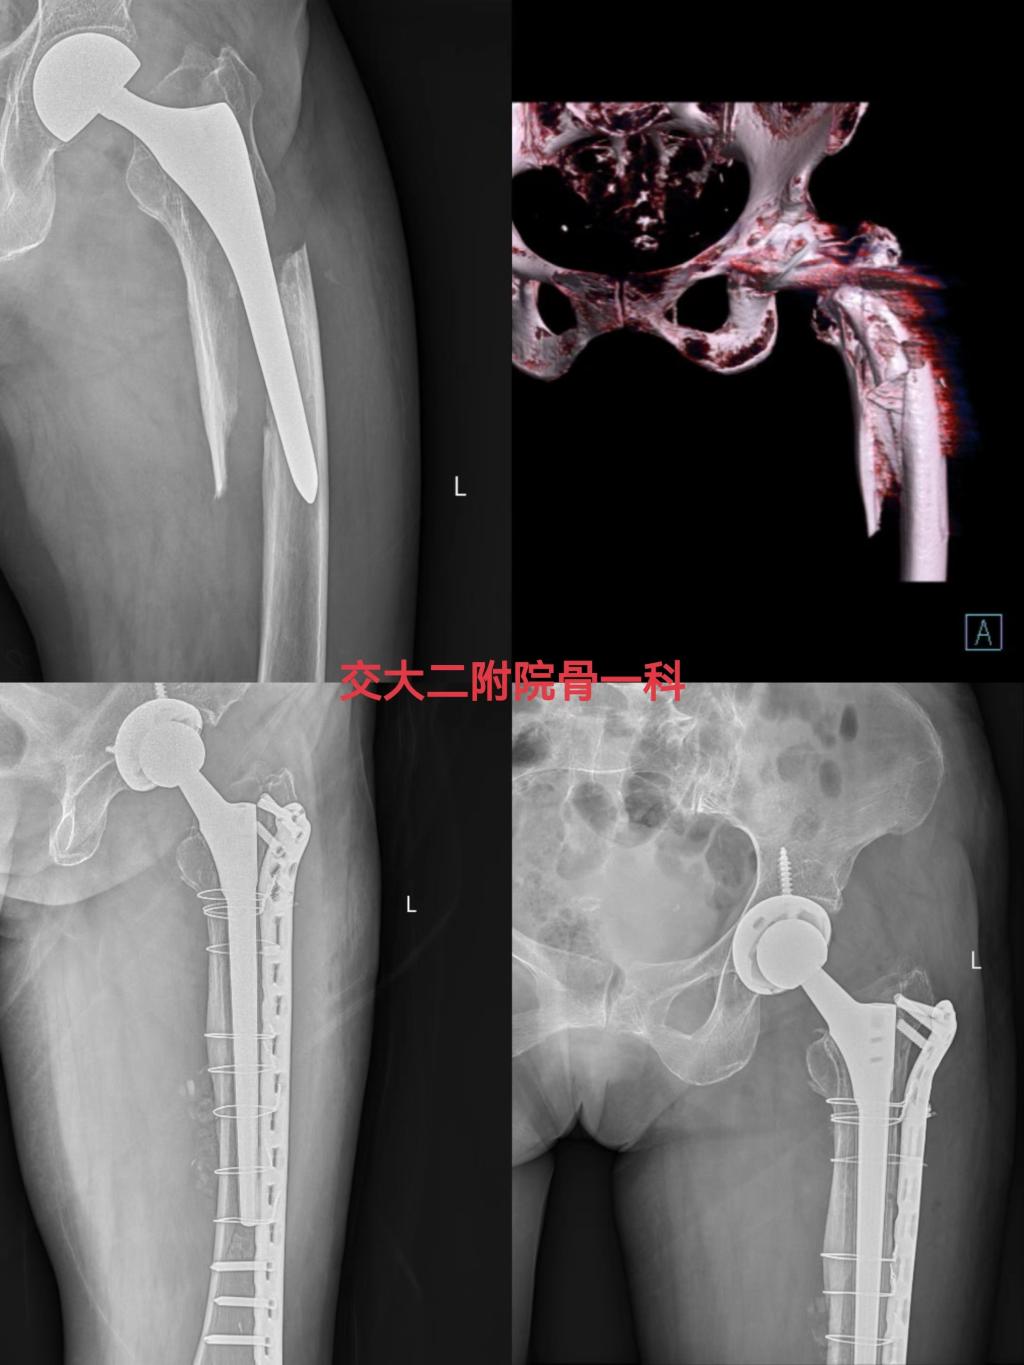

近期,骨一科收治多例需要进行髋关节复杂初次置换和翻修的患者,且病情复杂,手术难度大,党晓谦主任和时志斌副主任高度重视,组织全科对患者病情进行讨论分析,借助3D打印技术和计算机模拟手术技术,最终确定手术方案,在党晓谦主任的主刀下,手术顺利完成,术后患者恢复良好,均已顺利出院康复。

一位女性老年患者因“左人工股骨头置换术后5年,摔伤致左髋部疼痛活动受限3天”诊断入院,诊断为左侧股骨假体周围骨折(VancouverB3型),左侧人工股骨头置换术后,骨质疏松症,完善相关检查排除手术禁忌后,由时志斌副主任主刀完成左髋关节假体翻修手术,术后恢复良好,已顺利出院。